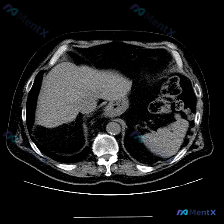

- 检查方式:单张上腹部CT横断面(软组织窗)

- 影像描述:

- 脾脏:形态正常,实质密度均匀,未见梗死、囊肿或占位性病变

- 肝脏:实质密度尚均匀,未见明显占位,肝轮廓光整

- 其他:胃壁未见明显增厚,腹腔无游离积液,腹膜后未见肿大淋巴结;腹主动脉管壁可见少许斑片状钙化,管径正常

- 影像结论:本层面未见明显病理性改变